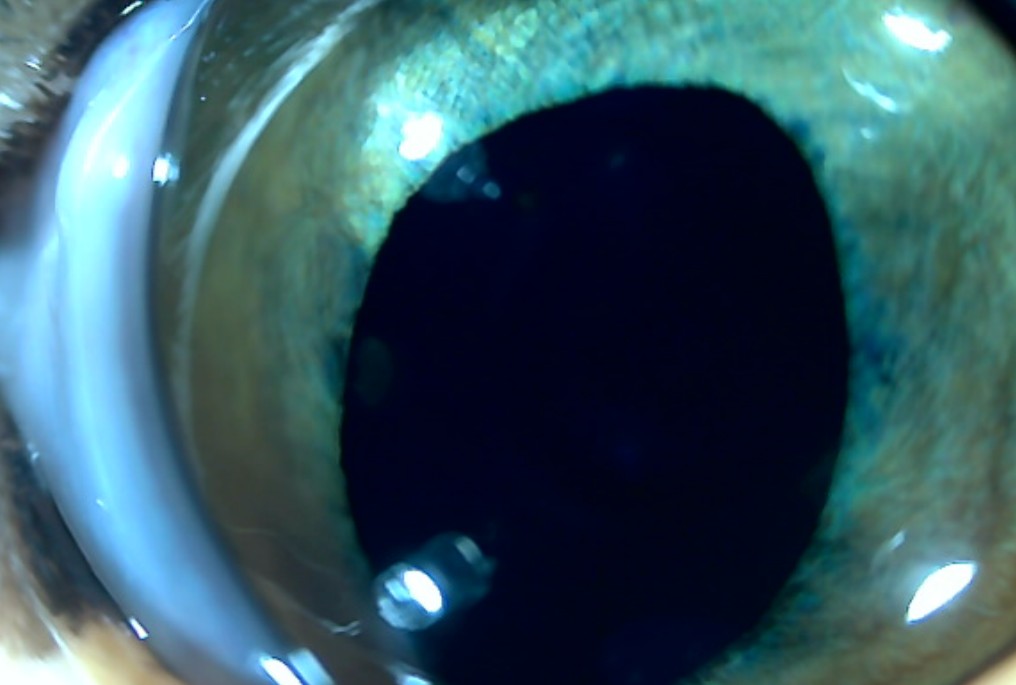

혈액검사에서는 주요 장기 수치, 염증 수치, 전해질 균형 등을 확인했고, X-ray는 흉부·복부 전반의 장기 구조를 점검했습니다. 초음파는 장기 실질 구조나 미세한 이상까지 확인할 수 있어 검진의 핵심 항목으로 포함됩니다. 치과검사는 일반적으로 마취가 동반되어, 구강전용 엑스레이 촬영을 해야 정확한 판단이 가능하지만 치과전문 병원인 만큼 육안으로 기본적인 검사는 해드리고 있습니다.

건강검진 항목에는 기본적으로 혈액검사, 흉부·복부 영상 검사, 갑상선·심장 관련 체크 등 마취 없이 진행 가능한 프로젝트들이 포함됩니다. 반면 치과 검진은 본격적인 확인을 위해 전신마취가 필요하기 때문에 종합검진 항목에서 제외되는 것이 일반적입니다. 물론 보호자께서 궁금해하시는 부분에 대해서는 외부 치아의 상태를 육안으로 간단히 확인해 드릴 수 있습니다.